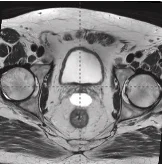

161 cc prostate post-MRI showing BioProtect Balloon Spacer, prostate, and rectum.

Post-MRI

Image courtesy of Dr. Shawn Zimberg, Radiation Oncologist.